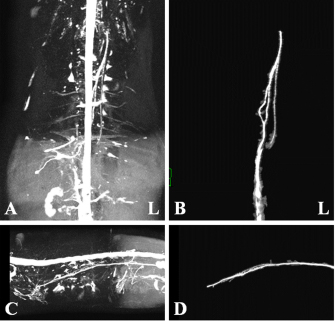

Fig. 1. Maximum intensity projection imaging of magnetic resonance thoracic ductography (MRTD). Cerebrospinal fluid, pleura, and kidney (renal pelvis) are shown (A, C). Unnecessary fluids were removed to construct the 3D image of MRTD (B, D). (A) Unprocessed MRTD image of the dorsal plane. (B) Processed MRTD image of the dorsal plane. (C) unprocessed MRTD image of the sagittal plane. (D) Processed MRTD image of the sagittal plane.

The raw MRI and CT data were transferred to a workstation (VAZE: PetCommunications, Chuo, Osaka, Japan) to construct the 3D images. In the MRTD images, the cerebrospinal fluid, pleura, kidney (renal pelvis) (Fig. 1A and C), part of the vessels (caudal vena cava, hepatic vein, and portal vein), and gastric juice were shown. Unnecessary fluids were removed in the maximum intensity projection (MIP) imaging of MRTD (Fig. 1B and D). Furthermore, 3D image of the thoracic duct was reconstructed from MRTD images, and 3D images of bone, heart, vessel, and esophagus were reconstructed from CT images. Those images were superposed using the “fusion” function on the workstation. The cerebrospinal fluid, kidney (renal pelvis), aorta, and liver vein (hepatic vein and portal vein) were used as indices of the superpose methods (Fig. 2A–C). The number of thoracic ducts at each vertebra between C5 andL2 were recorded in transverse MRTD (Fig. 2C) and T2WI (Fig. 2D). Location in relation to aorta and the location of the branches of thoracic duct were noted where possible. The comparison of the number of thoracic ducts at each vertebra between transverse T2WI and MRTD was performed using Student’s t-test. Statistical significance was set at p < 0.05.

The thoracic ducts were identified in MRTD images acquired from all of the dogs (Figs. 36). The average number of thoracic ducts at each vertebra between C5 and L2 is summarized in Table 1. The thoracic ducts in all dogs coursed along the right-dorsal side of the aorta, cranially from the L2 level (Fig. 6). Thereafter, these bent to the left side at the aortic arch and curved at the left external jugular vein angle (Fig. 6). The thoracic ducts between C5 and C7 were not found on images of any of the dogs (C5: all dogs, C6: 3 dogs, and C7: 1 dog) (Fig. 5 and Table 1). Thoracic duct branches of dogs were shown at levels between T4 and L1 (Fig. 5 and Table 1). Thoracic duct branches located on the left-dorsal side of aorta were confirmed in four dogs (except dog 2) (Fig. 6). Only dog 2 showed a branch of the thoracic duct to the ventral side that formed a ring (Fig. 4). The right lymphatic duct was not found on images in all dogs. A comparison of the number of thoracic ducts at each vertebra between transverse T2WI and MRTD did not reveal any significant differences for all vertebrae (Table 1).

In this study, we provide evidence that our MRTD technique using the SS-FSE sequence modified for application in the mediastinum could aid in visualization of the thoracic duct. In a previous study using MRI in dogs, cisterna chyli and thoracic duct were visible as hyperintense structures on T2WI (Johnson and Seiler, 2006). This study also showed that the signals from liquid fractions were, especially, prominent on T2WI, and the other signals were dampened based on the principle that lymph flowing through the thoracic duct appears hyperintense. SS-FSE sequence is used for MR myelography in veterinary practices (Pease et al., 2006), which shows only cerebrospinal fluid due to a lack of signal from any substances except pure fluid. Normal SS-FSE of thorax is severely affected by artifacts produced by breathing-related movements. In our MRTD technique, SS-FSE sequence with respiratory gating was set to prevent motion artifacts due to breathing and led to significant improvement in the visualization of the thoracic duct. MRTD using the SS-FSE sequence also enabled 3D visualization, including MIP images by scanning consecutive thin imaging planes. The resolution of the SS-FSE sequence (spatial resolution=1 × 1 mm) was lower than that of transvers T2WI (spatial resolution=0.5×0.5 mm). In our study, the number of thoracic ducts depicted on MRTD was similar to that observed on transverse T2WI. Therefore, 3D-MRTD may be a superior method for the examination of 3D thoracic configuration.